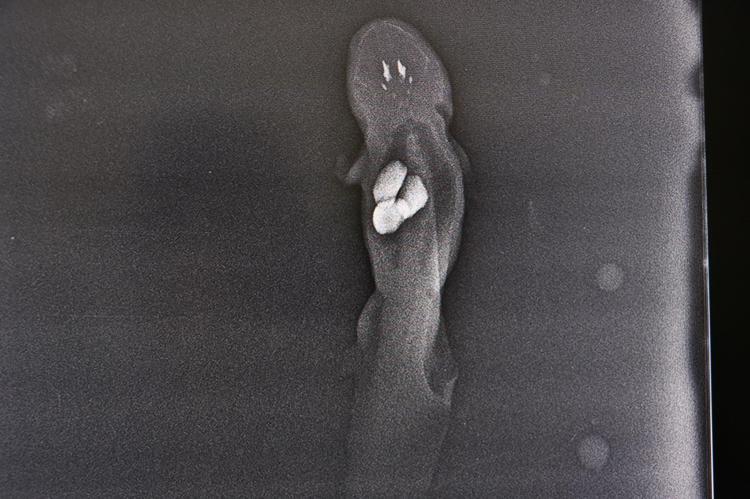

Kentte yaşayan bir kişi, Türkiye’de nadir yetiştirilen aksolotl balığının akvaryumdaki taşları yuttuğunu fark etmesi sonrası balığını Erciyes Üniversitesi Veteriner Fakültesi Hayvan Hastanesi’ne götürdü. Yapılan muayene ve çekilen röntgenlerde, balığın midesinde yaklaşık 1’er santimetre büyüklüğünde 3 taş olduğu belirlendi. Balık, anestezi uygulanarak ameliyata alındı. Cerrahi operasyon sonrası taşlar çıkarıldı. Operasyonun ardından balık, sahibine teslim edildi.

Operasyon sürecini anlatan veteriner hekim Esma Erer, “Bu yaptığımız operasyon, Türkiye’de ilk değil. Daha önce aynı vaka ile başka üniversitelerde kliniğe başvurulmuştur. Akvaryumda bir süs balığı olarak yetiştirilen 'Axolotl (aksolotl)' balığı çakıl taşlarını yutması ve sindirim sistemi problemiyle kliniğimize getirildi. Röntgen ve klinik muayeneler neticesinde yaklaşık 1 santimetre boyutunda 3 adet taş tespit edildi. Bunun sonucunda balığın ameliyatla midesindeki yabancı cismin çıkarılmasına karar verilmiştir. Balık anestezi altında su içerisinde karın bölgesinden yaklaşılarak mideye ulaşıldı. Daha sonra mide açıldı ve balığın midesi içerisindeki 3 adet yabancı cisim çıkarıldı. Yabancı cisim çıkarıldıktan sonra hayvan uyandırıldı. Daha sonra da hasta sahibine teslim edildi. Sonrasında ise hasta sahibi düzenli olarak kontrole getirdi. Şu anda ise balığın durumunun gayet iyi olduğunu biliyoruz” diye konuştu.